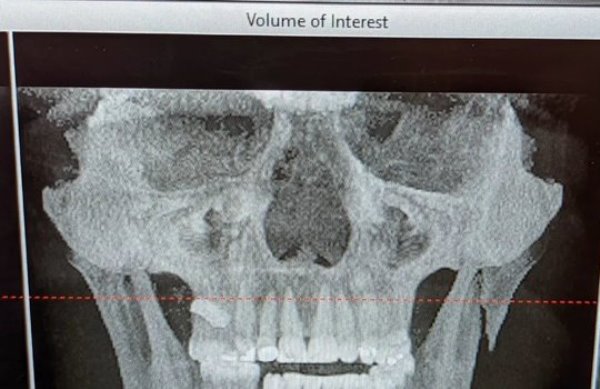

«Упс! Кажется, стоит немного подлечиться и попить молока», — написал Полицци, опубликовав снимок своей челюсти в соцсетях.